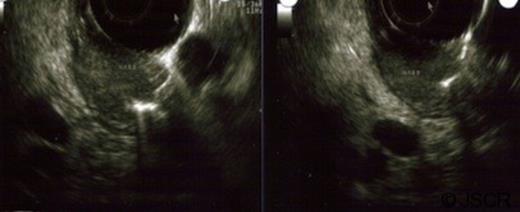

A 66 year-old woman was referred to the surgeon’s office when she presented with a five month history of upper abdominal pain and diarrhoea. A CT scan of the abdomen and pelvis obtained upon presentation to the emergency department showed intrahepatic and extrahepatic bile duct dilatation. There were no masses in the cystic bile duct (CBD) or the pancreas. This was followed by an oesphago-gastro-duodenoscopy (OGD) that showed a prominent ampulla (Figure 1) with very hard tissue suspicious for malignancy. On oesophageal ultrasound, there was a submucosal mass, isoechoic, not invading the muscularis propria (Figure 2), and without involvement of the pancreas. There were no enlarged lymph nodes. The biopsy specimen was positive for a focal carcinoid tumor on a background of duodenitis. The cells stained positive for Chromogranin, Synaptophysin and Cytokeratin.